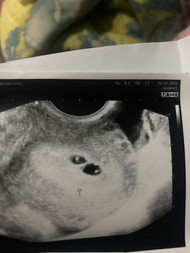

ไปรพ. ตอน5สัปดาห์3วัน อัลตร้าผ่านทางช่องคลอด แต่ไม่เจออะไรเลยค่ะ แม้แต่ถุงตั้งครรภ์ก็ไม่เจอ แม่ๆคนไหนมีประสบการณ์มาแชร์ข้อมูลได้นะคะ

หมอได้ทำการ อัลตร้าซาวด์ ผ่านหน้าท้อง และ ช่องคลอด ในเครื่อง อัลตร้าซาวด์ บอกอายุครรภ์ว่า 7 สัปดาห์ 6 วัน แต่ถุงการตั้งครรภ์จริงๆ เล็กมากๆ เจอไข่แดง ตั้งครรภ์ในมดลูกปกติ หมอนัดอีก 2 สัปดาห์ เพื่อมาอัลตร้าซาวด์ แบบนี้ ผิดปกติไหมคะ กังวลมากๆเลยคะ 😢🥺 รอบประจำเดือนคือ วันที่ 2 ธันวาคม หมดวันที่ 9 ธันวาคม พ.ศ. 2568 ระยะเวลา 8 วัน รอบเดือน ยาว 35 - 36 วัน เป็นไปได้ไหมคะ ที่ไข่จะตกช้า